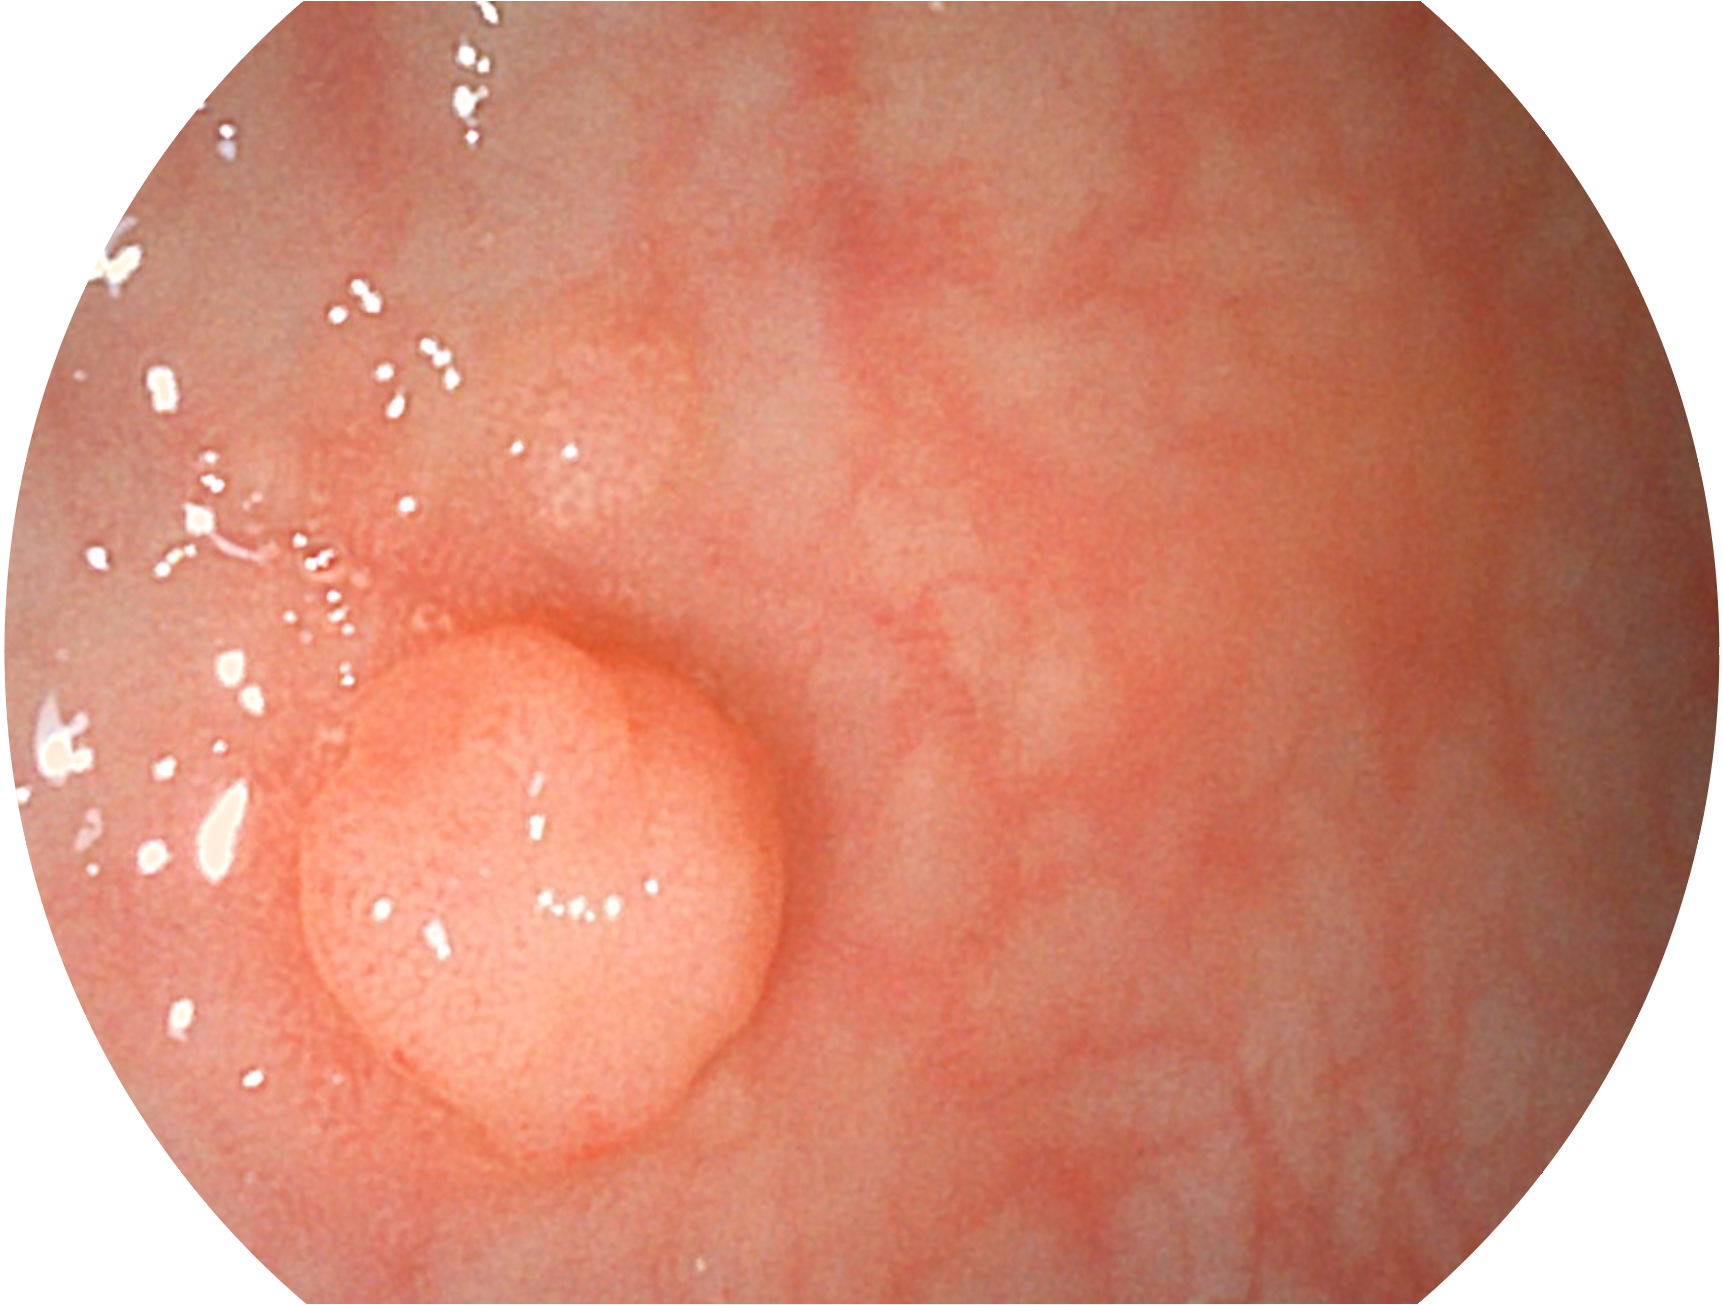

百老汇电子游戏官网新开发的内镜染色技术,主要是基于多波长LED 光源的开发,VLS-55Q 四波长LED 光源是由四个不同颜色的LED光按照相应照明模式所规定的特定发光比例进行合束后形成,合束后形成的照明光的光谱由红光、绿光、蓝光及蓝紫光这四个不同的波段范围构成。具有更高光谱自由度,通过光谱比例的控制,实现了聚谱成像技术,英文全称为“Spectral Focused Imaging, SFI”,缩写为“SFI”和光电复合染色成像技术,英文全称为“Versatile Intelligent Staining Technology, VIST”,缩写为“VIST”。